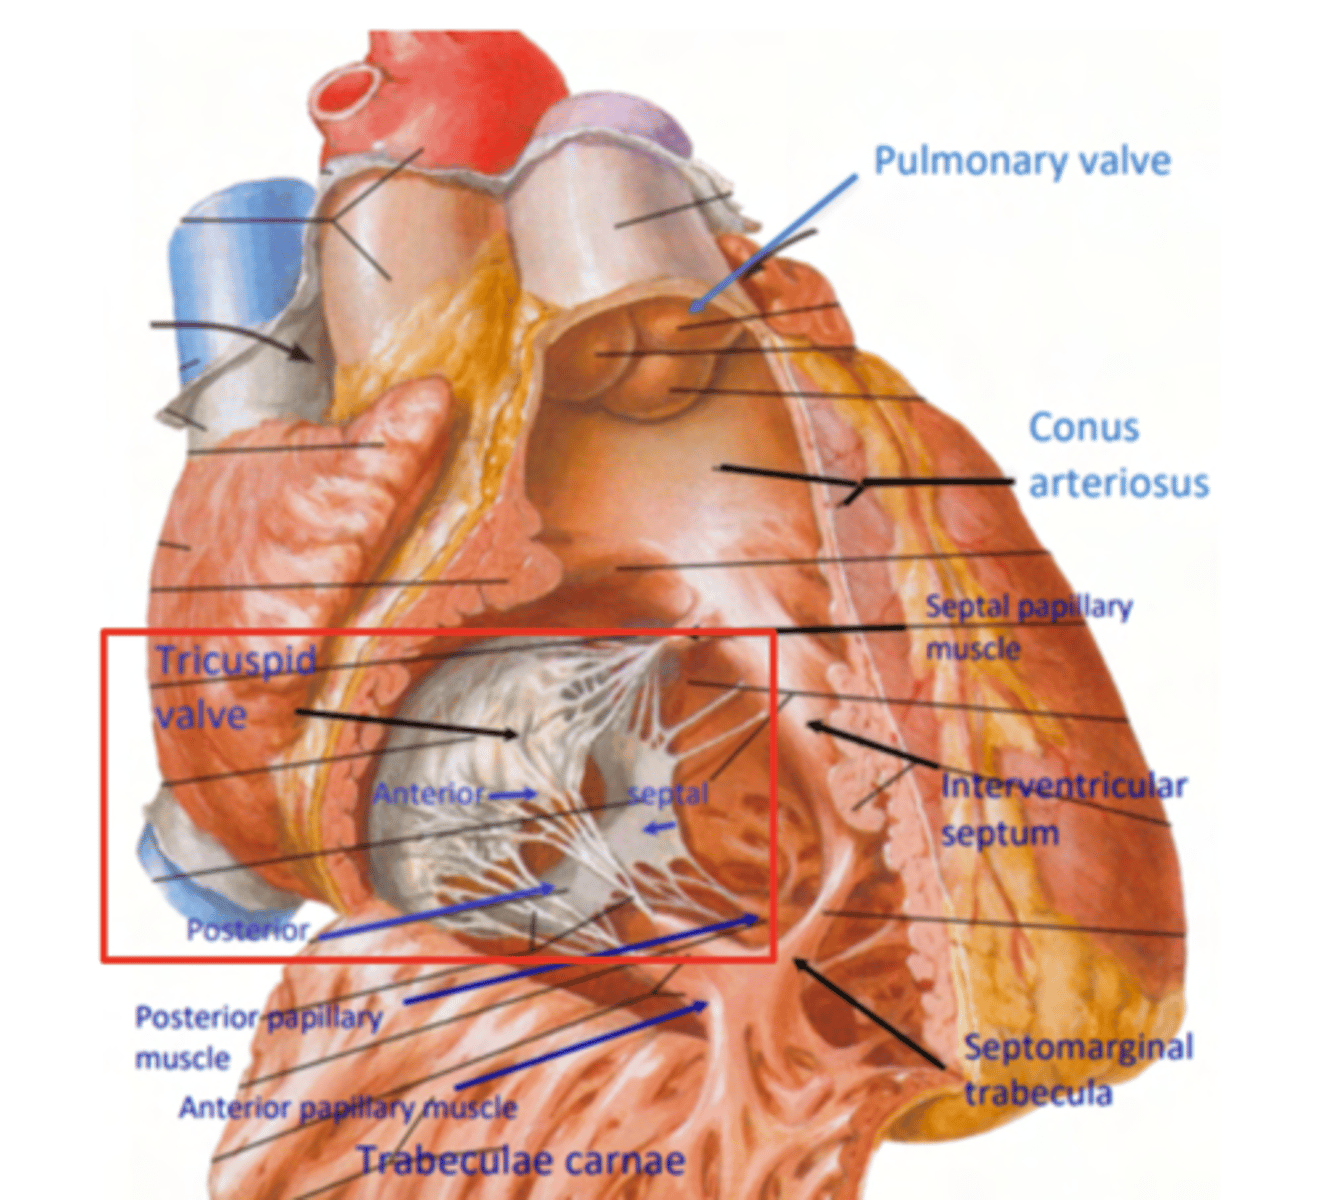

Describe the two portions of the medial/septal face/wall of the right ventricle.

infundibulum or outflow region or conus arteriosus (smooth and membranous)

trabeculae carnae (muscular and irregular)

What are the 3 cusps of the tricuspid valve?

Anterior

Posterior

Septal

What connect the cusps of the valve a to papillary muscles in the

right ventricle?

Chordae tendinae

With the contraction of the walls of the ventricle what's the action of the papillary muscles?

contract as well

With the contraction of papillary muscles what will be happen with the valve?

Close

What is the septomarginal trabeculae (or moderator band)?

What role do the papillary muscles and chordae tendineae play in the function of the tricuspid valve?

During ventricular systole (contraction), the tricuspid valve closes

The papillary muscles contract at the same time as the ventricle.

This contraction tightens the chordae tendineae, pulling the valve leaflets taut and holding them in place.

This mechanism prevents the valve leaflets from prolapsing (bulging back) into the atrium under the high pressure of ventricular contraction.